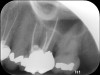

Clinical procedure: If apical bone loss is present (Figure 1) a collagen/gelatin sponge (eg, Gelfoam®, Pfizer Inc., www.pfizer.com) can be placed apically so that the MTA can be delivered to the desired working length. (Any other surgical resorbable sponge would also work, such as OraPlug® [Salvin Dental Specialties, www.salvin.com], Surgifoam® [Midwest Dental, www.mwdental.com], or Surgispon® [Aegis Lifesciences, www.surgispon.com]). This is done by taking a small piece (2 mm x 2 mm) of the resorbable sponge and pushing it down to and through the root apex with an endodontic file. Once this is done, MTA is packed down the canal with a custom-fitted cone. The clinician can use a rubber stopper on the gutta-percha cone to know the exact length of MTA placed in the apical third (Figure 2). Once the apical third is sealed with 3 mm to 5 mm of MTA, the remaining coronal canal space can be back-filled using a warm gutta-percha technique (Figure 3).

Fig 1. Preoperative radiograph showing apical bone loss.

Figure 1